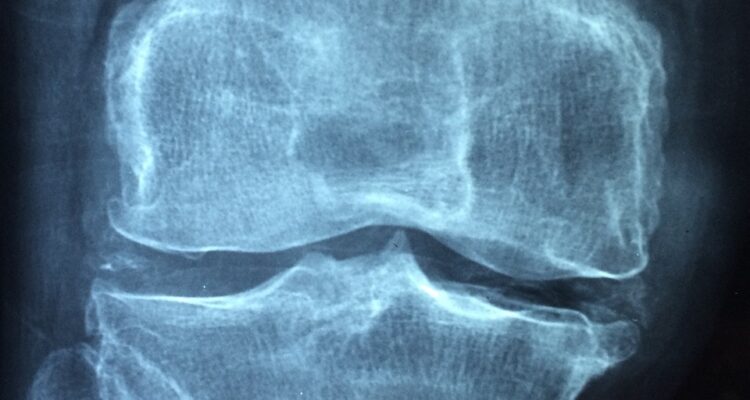

Le cartilage est l’un des tissus composant les articulations, mais malgré l’importance de ces dernières, ce tissu est l’un de ceux dont la production diminue le plus avec l’âge, ce qui peut également être dû à l’épuisement des ressources, à la malnutrition et au stress chronique. L’usure de ces derniers, ainsi que d’autres composants des articulations, entraîne de l’arthrose et, par conséquent, de graves douleurs et souffrances. Découvrez dans cet article de Detective-Sante les principaux aliments pour régénérer le cartilage des articulations afin que vous puissiez y parvenir de manière naturelle et saine.